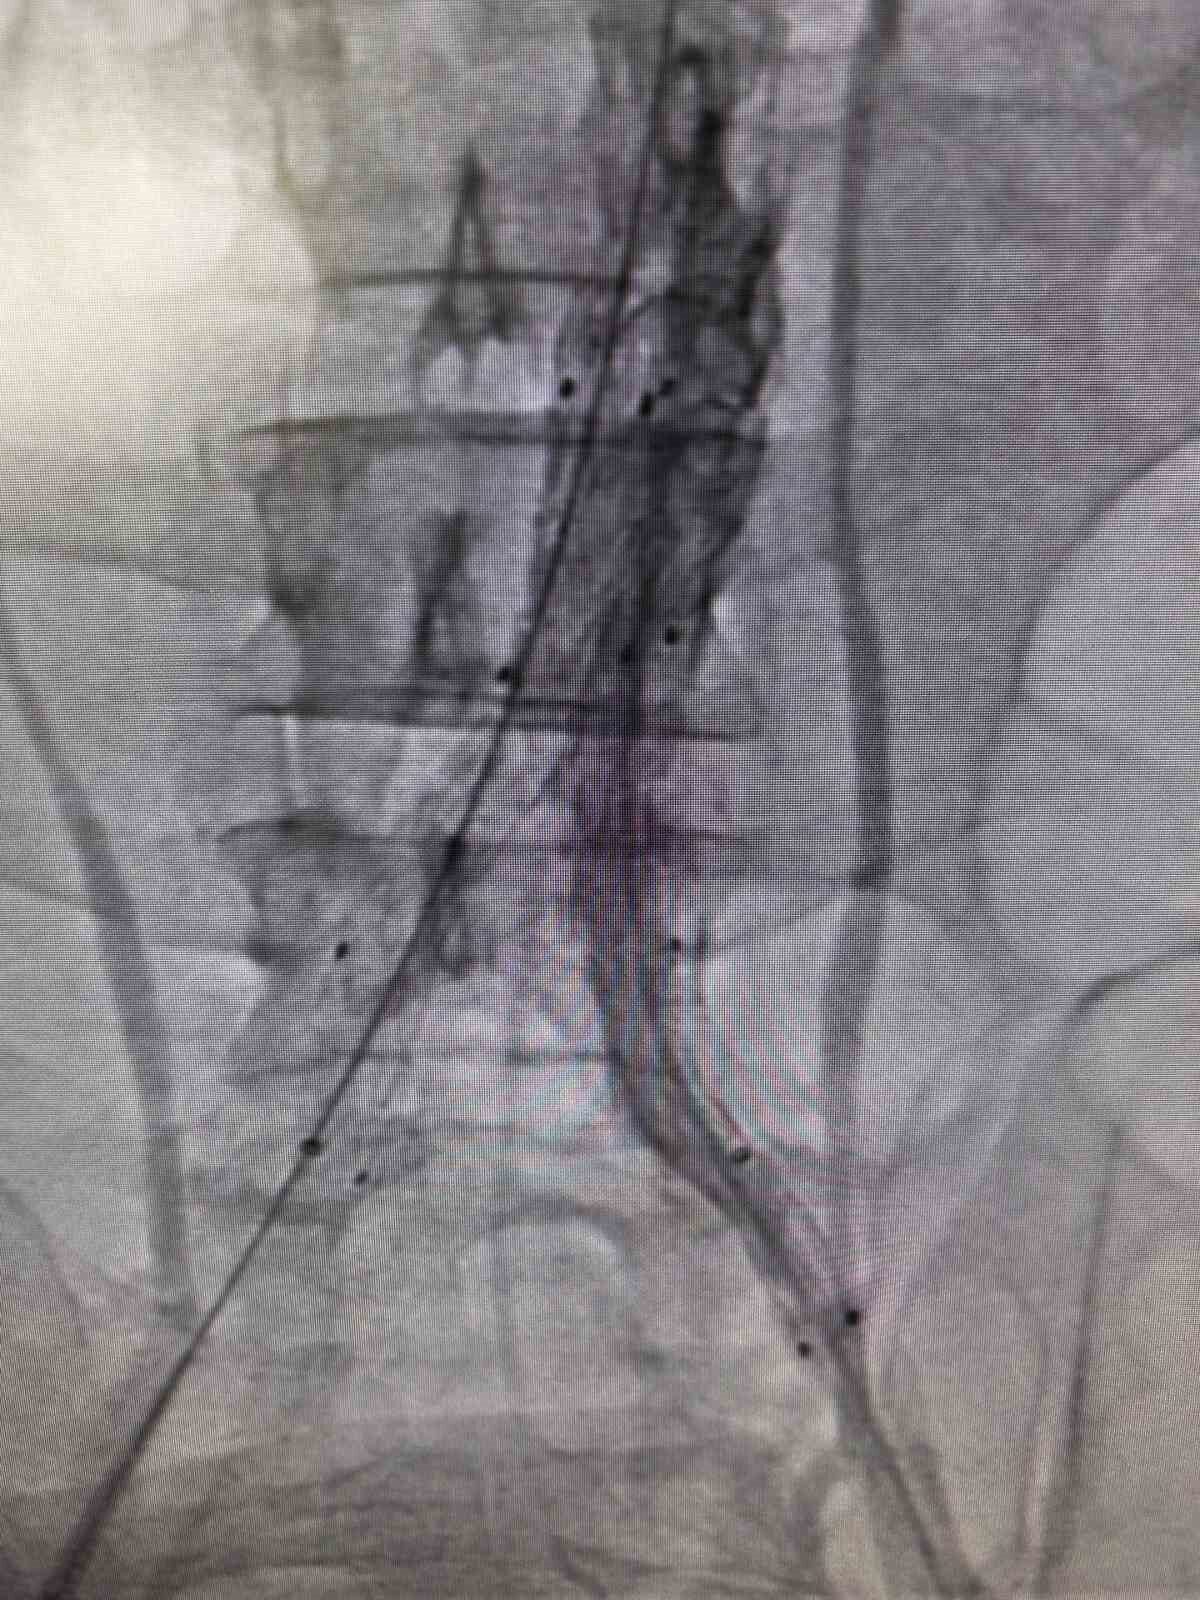

Bilecik Eğitim ve Araştırma Hastanesi’nde daha önce farklı sağlık kuruluşlarına başvuruda bulunan ve kesin bir tanı konulamayan hasta, acil serviste gerçekleştirilen detaylı tetkiklerle doğru tanıya ulaştırıldı. Şiddetli sırt ve karın ağrısı şikayetiyle hastaneye gelen 39 yaşındaki Mehmet D.’nin acil serviste çekilen ileri görüntüleme tetkiklerinde, kalpten çıkan ana damarın iç duvarında yırtık olduğu belirlendi. Hayati risk taşıyan bu durum nedeniyle hasta, kalp ve damar cerrahisi ekibi tarafından acil olarak değerlendirildi. Hasta, Kalp ve Damar Cerrahisi Uzmanı Op. Dr. Elmas Üreyen tarafından kapalı yöntemle tedavi edildi. Damar içinden girilerek gerçekleştirilen işlem sırasında, yırtılan ana damarın içine özel bir stent yerleştirildi ve damar içten onarıldı. Açık ameliyata gerek kalmadan yapılan bu uygulama sayesinde hasta kısa sürede rahatladı. Tedavi sonrası yakından izlenen hastanın ağrılarının tamamen geçtiği ve genel sağlık durumunun iyi olduğu gözlemlendi. Kontrollerinin sorunsuz geçmesi üzerine hasta sağlıklı bir şekilde taburcu edildi.

Konuyla ilgili açıklama yapan Op. Dr. Elmas Üreyen, “Bu tür damar yırtılmaları ani gelişebilen ve zamanında müdahale edilmezse hayati risk taşıyan durumlardır. Hastamızda erken tanı koyarak kapalı yöntemle müdahale ettik. Açık ameliyata gerek kalmadan yapılan bu işlem, hastanın hem daha hızlı iyileşmesini hem de günlük yaşamına kısa sürede dönmesini sağladı. Hastanemizde, ileri teknoloji tıbbi cihazlar ve deneyimli hekim kadrosu ile bu tür yüksek riskli damar hastalıklarının tanı ve tedavisi başarıyla gerçekleştirilmektedir. Kapalı yöntemlerle uygulanan bu tedaviler, hastalara daha konforlu bir süreç sunarken, iyileşme süresini de önemli ölçüde kısaltmaktadır” dedi.